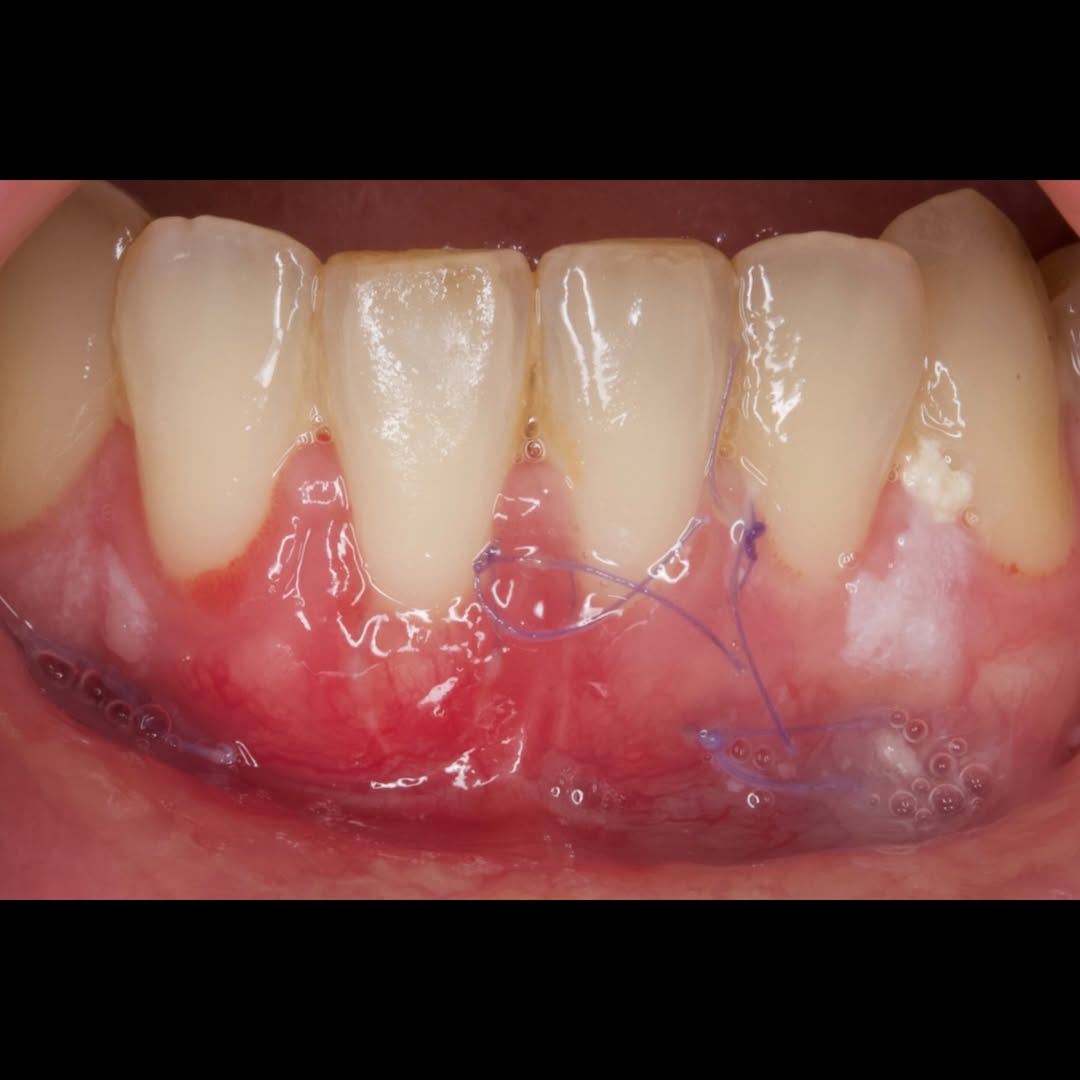

Durante una mañana, asistirás a una Cirugía Mucogingival de recubrimiento radicular de recesiones múltiples en IV y V sextante (36 a 43).

Gracias al uso del microscopio y a la proyección en tiempo real en pantalla, verás exactamente lo mismo que veo yo durante la cirugía, sin tener que estar

Aprende la planificación y técnica de la cirugía Mucogingival para el recubrimiento de recesiones y aumento de banda queratinizada en el sector anteroinferior

Durante una mañana, asistirás a una Cirugía Mucogingival de recubrimiento radicular de una recesión unitaria en 31 con frenillo asociado. Gracias al uso del microscopio y a la proyección en tiempo real en pantalla, verás exactamente lo mismo que veo yo durante la cirugía, sin tener que estar

Una estancia clínica pensada para quienes quieran iniciarse o dar un paso más en el campo de la cirugía mucogingival. Durante esta experiencia tendrás la oportunidad de aprender en directo cómo se planifica y se lleva a cabo una cirugía mucogingival mediante técnica de Túnel.

La sesión